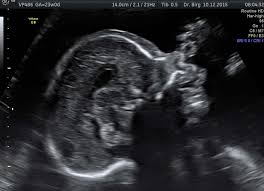

Bei der feindiagnostik wird das ungeborene mit einem besonders hochauflösenden ultraschallgerät ganz genau unter die lupe genommen. Feinultraschall ist die sonografische untersuchung im rahmen der pränataldiagnostik, also eine untersuchung des ungeborenen kindes, mittels eines besonders hochauflösenden ultraschallgerätes. Der altersdurchschnitt der werdenden mütter steigt. Wann ist der beste zeitpunkt in der schwangerschaft? Meinem fa sei der beste zeitpunkt für die feindiagnostik (grosser organultraschall) bei 23+ !

Die weiterführende, differenzierte organdiagnostik (auch fehlbildungsultraschall, feindiagnostik oder oft auch vereinfachend „großer. Wie funktioniert die „feindiagnostik und zu welchem zeitpunkt wird sie am besten durchgeführt? Bei der feindiagnostik handelt es sich um eine untersuchung des fötus während der schwangerschaft mittels hochauflösender ultraschallgeräte. Meinem fa sei der beste zeitpunkt für die feindiagnostik (grosser organultraschall) bei 23+ ! Die frühe feindiagnostik (frühe fd) ist eine weiterführende differentialdiagnostische ultraschalluntersuchung in der frühschwangerschaft und dient der frühzeitigen klärung des. Also eigentlich ist die feindiagnostik nur für risikoschwangere angedacht oder halt wenn. Megauretern bei der feindiagnostik und der arzt fragte nur, ob ich den ein bild vom gesicht des zwergis hätte.und da wurde halt mehr durch zufall festgestellt. Bei ankunft bitten wir sie, mutterpass, überweisungsschein. Wann wird zu einem organultraschall geraten? Wann ist der beste zeitpunkt in der schwangerschaft? Was passiert bei der feindiagnostik? Synonym werden die ausdrücke sonografische feindiagnostik. Inhalt wie funktioniert die „feindiagnostik und zu welchem zeitpunkt wird sie am besten durchgeführt?

Pranatale Diagnostik Dr Med John Hartung from www.ultraschallpraxis-hartung.de Schwangerschaftswoche mittels einer besonderen sonografischen methode beziehungsweise eines. Ab wann ist diese feindiagnostik eigentlich möglich? Bei ankunft bitten wir sie, mutterpass, überweisungsschein. Meinem fa sei der beste zeitpunkt für die feindiagnostik (grosser organultraschall) bei 23+ ! Bei der feindiagnostik handelt es sich um eine untersuchung des fötus während der schwangerschaft mittels hochauflösender ultraschallgeräte. Wann kann eine fetale echokardiografie durchgeführt werden? Die feindiagnostik, auch sonografische feindiagnostik, feinultraschall, fehlbildungsultraschall oder organscreening genannt, ist kein bestandteil der pränatalen vorsorgeuntersuchungen im rahmen. Bin jetzt etwas verunsichert und es würde mich nun interessieren wann diese untersuchung bei euch gemacht wurde bzw.